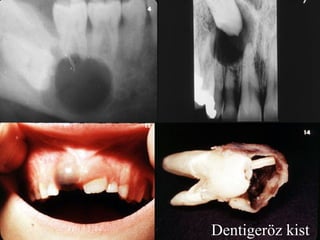

ÇENE KİSTLERİ | PPT